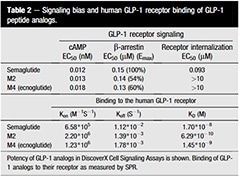

Recombinant drug targets have been crucial in drug development and disease discovery. Guo et al. used the recombinant human GLP-1 receptor protein from Sino Biological (Cat#: 13944-H02H) to discover and characterize ecnoglutide (XW003), a novel GLP-1 analog.

The surface plasmon resonance (SPR) technique was used to measure the kinetics of the binding of GLP-1 peptide analog to the human GLP-1 receptor (Cat#: 13944-H02H, Sino Biological). Image Credit: Wanjun Guo et al.